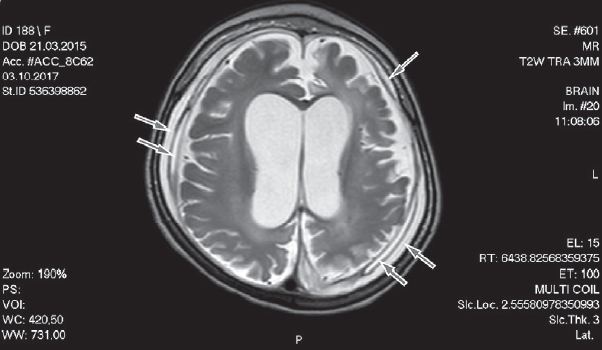

Пациентка 2 (девочка, 2 года 7 месяцев) поступила в микрохирургическое отделение СПбГПМУ с жалобами на значительное отставание в психомоторном развитии и эпилептические приступы. Из анамнеза известно, что беременность протекала на фоне хронической урогенитальной инфекции. Роды вторые срочные, путем операции кесарева сечения на фоне вторичной родовой слабости, начавшейся интранатальной асфиксии плода. Вес при рождении 3200 г. С рождения мама отмечает задержку психомоторного развития. В возрасте 2 месяцев отмечен первый судорожный приступ, на фоне повышенной температуры тела, обструктивного бронхита с дыхательной недостаточностью 2–3-й степени, сердечно-сосудистой недостаточностью 1–2-й степени. Девочка госпитализирована в реанимационное отделение Российской детской клинической больницы. Отмечались повторные афебрильные судорожные приступы. Ребенок наблюдался у инфекциониста в связи с генерализованной формой врожденной миксгерпетической вирусной инфекцией (I, IV, V типов), хроническое течение (гепатит, энцефалопатия, лимфаденопатия, спленомегалия); вторичной иммунной недостаточностью. При поступлении в клинику СПбГПМУ у ребенка сохранялись судорожные приступы в виде эпизодов тонического напряжения конечностей с отведением глазных яблок кверху, ежедневно. Получала антиэпилептическую терапию (Леветирацетам по 40 мг/кг в сутки). Пациентке проведена МРТ головного мозга: МР-признаки двусторонних хронических субдуральных гематом. Глиозно-атрофические изменения белого вещества обеих гемисфер головного мозга, больше справа. Смешанная заместительная гидроцефалия. Mega cisterna magma. Микроцефалия. Данные МРТ представлены на рис. 3. По результатам комплексного мультимодального обследования установлен диагноз: «Органическое поражение центральной нервной системы. Хронические двухсторонние субдуральные гематомы. Атрофические изменения белого и серого вещества обеих гемисфер головного мозга. Смешанная заместительная гидроцефалия. Аномалия Денди – Уокера. Грубое отставание в психомоторном и речевом развитии. Спастический тетрапарез. Псевдобульбарный синдром. Структурная фокальная эпилепсия. Частичная атрофия зрительных нервов обоих глаз. Умеренная спленомегалия». В клинической больнице СПбГПМУ выполнено оперативное вмешательство: костно-пластическая краниотомия, проведено удаление хронических многоуровневых субдуральных гематом справа. По данным послеоперационной мультиспиральной компьютерной томографии, сохранялась заместительная гидроцефалия на фоне атрофических изменений головного мозга. В сравнении с предоперационным исследованием отмечалось уменьшение объема субдуральной гематомы справа. В послеоперационном периоде судороги купированы. Проведен контроль ЭЭГ в послеоперационном периоде: регистрировался уплощенный фоновый паттерн, замедление возрастного ритма. Регистрировались единичная вспышка региональной эпилептиформной активности, высокоамплитудные деформированные комплексы «острая волна — медленная волна» в передних областях правого полушария. Пациентка с улучшением неврологического состояния, купированием эпилептических приступов (клинико-энцефалографическое улучшение на фоне продолжения антиэпилептической терапии Леветирацетамом в дозе 40 мг/кг в сутки) выписана на амбулаторное лечение под наблюдение невролога. В дальнейшем регистрировались редкие фокальные моторные приступы.

Рис. 3. Магнитно-резонансная томограмма головного мозга. Стрелками отмечены хронические многоуровневые субдуральные гематомы различной давности. Глиозно-атрофические изменения белого вещества обеих гемисфер головного мозга, заместительная гидроцефалия. Режим T2W.

Fig. 3. Magnetic resonance imaging of the brain. Arrows indicate chronic multilevel subdural hematomas of various prescription. Glio-atrophic changes in the white matter of both hemispheres of the brain, replacement hydrocephalus. T2W mode